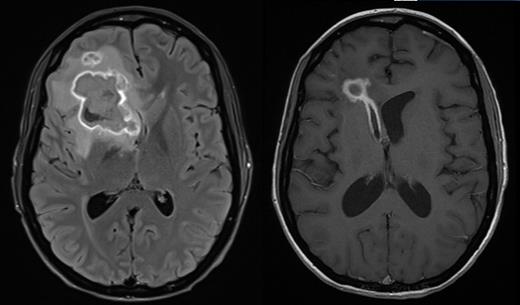

Patient A is a 27 year old female who underwent a myeloablative sibling haploidentical transplant for Philadelphia negative B-ALL in second remission. At day 100 she developed grade III lower GI GVHD requiring methylprednisolone and ruxolitinib for steroid dependent disease. Subsequent CMV reactivation was treated with ganciclovir. Cough in association with pulmonary infiltrates followed, and a bronchoalveolar lavage grew Scedosporium aurantiacum, Clavispora lusitaniaand Aspergillus fumigatus. She developed severe headache and MRI imaging showed a thin rim-enhancing 38x37 mm lesion within the right frontal lobe with moderate vasogenic oedema. Surgical drainage yielded 20 ml of frank pus that grew Scedosporium aurantiacum.

Antifungal therapy was started with vorinconazole, terbinafine, amphotericin and later caspofungin. Serial imaging after 12 days showed two new hyperdense foci representing extension of infection, consistent with worsening headaches. The patient received a single infusion of 3 rd party FSTs at a dose of 1 x10 6/m 2 at day 170 post-transplant while continuing antifungal therapy with vorinconazole and terbinafine. The product consisted of 94.1% CD4 +, 3.5% CD8 + T-cells and 1% NK cells and contained CD4 + T-cells responsive to both A. terreus and C. krusei antigens presented by HLA DR*03:01 shared between product and patient. There were no infusion related adverse events. Corticosteroids and calcineurin inhibitors were continued. Within one week of FST infusion there was an increase in the number of naïve and central memory CD4 + T-cells in blood and a fall in the number of CD4 + and CD8 + T-cells expressing Tim3. Over the following 3 months, there was a gradual rise in the number of CD4 + Tem and CD4 + Temra with a later and less pronounced rise in the analogous CD8 + populations. Serial imaging demonstrated rapid regression of the pulmonary abnormalities and gradual regression of the cerebral lesion at day 150 following FST infusion. 279 days after transplant and 109 days after infusion of FSTs, the patient developed worsening of headache and MRI confirmed rupture of the abscess into the right ventricle. Headache gradually resolved and the patient was discharged from hospital 329 days after transplant with ECOG 1 and no neurological abnormalities. However she was readmitted 13 days later with more severe headache with repeat imaging confirming raised intracranial pressure. CSF showed no evidence of fungi by PCR or culture. A CSF shunt was inserted and the patient remains well.